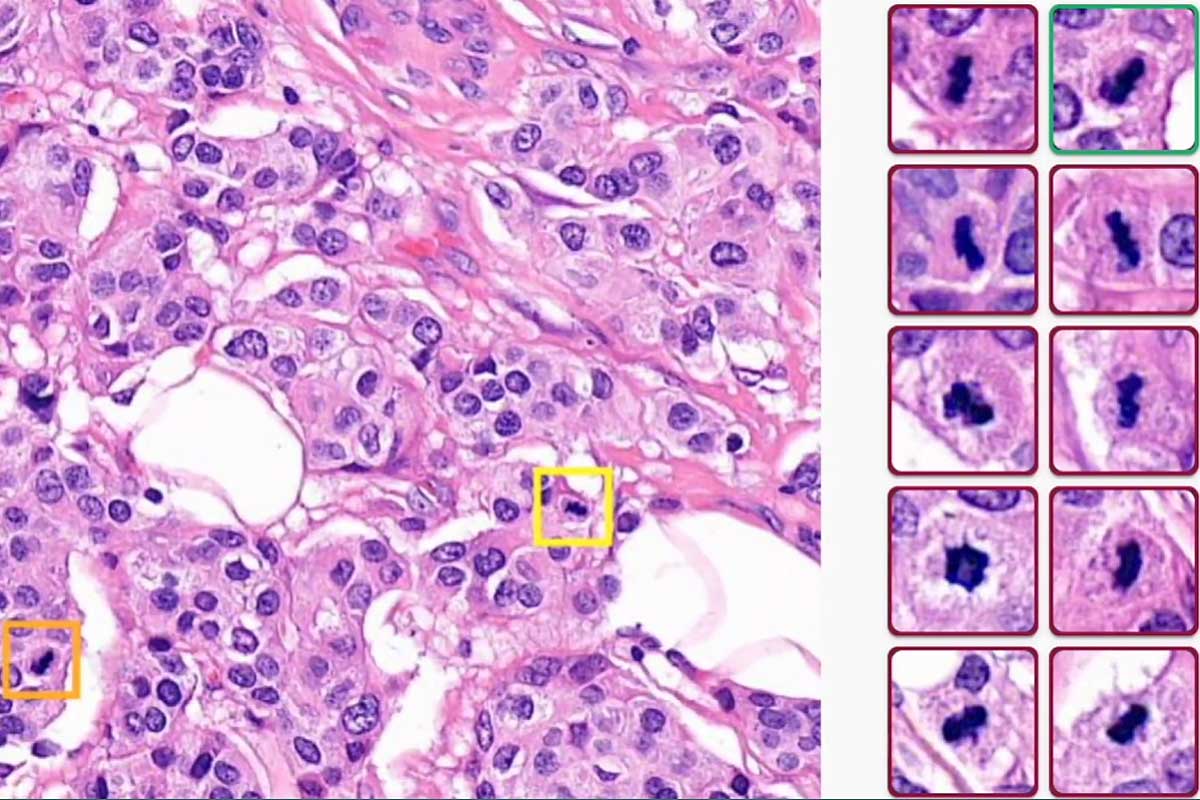

Détection de tous les objets de mitose et les points chauds de mitose dansles régions cancéreuses.

Détection de tous les objets de mitose et les points chauds de mitose dans les régions cancéreuses. Crédit photo : Primaa